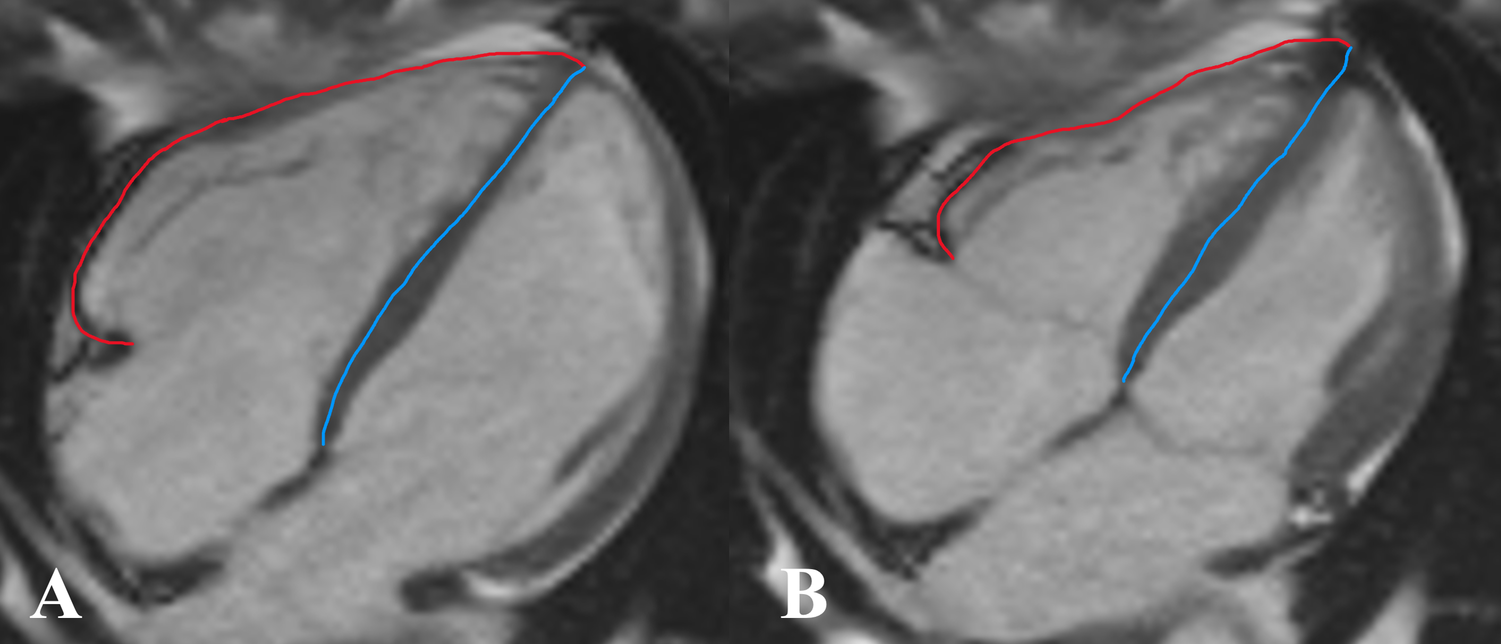

According to Zhang et al. (11), the right ventricular end-diastolic remodeling index (RVEDRI) and RVESRI are the ratio of the lateral free wall length to septal wall height in the end-systolic phase and end-diastolic phase which was measured on the long-axis four-chamber cine image of CMR (Figure 3) by a cardiovascular radiologist.

Figure 3

www.frontiersin.org

Figure 3. Measurement of right ventricular end-diastolic remodeling index (RVEDRI) (A) and right ventricular end-systolic remodeling index (RVESRI) (B) on the four-chamber cine image of cardiac magnetic resonance imaging (CMR). RVEDRI and RVESRI were the ratios of lateral free wall length (red line) to interventricular septal height (blue line).